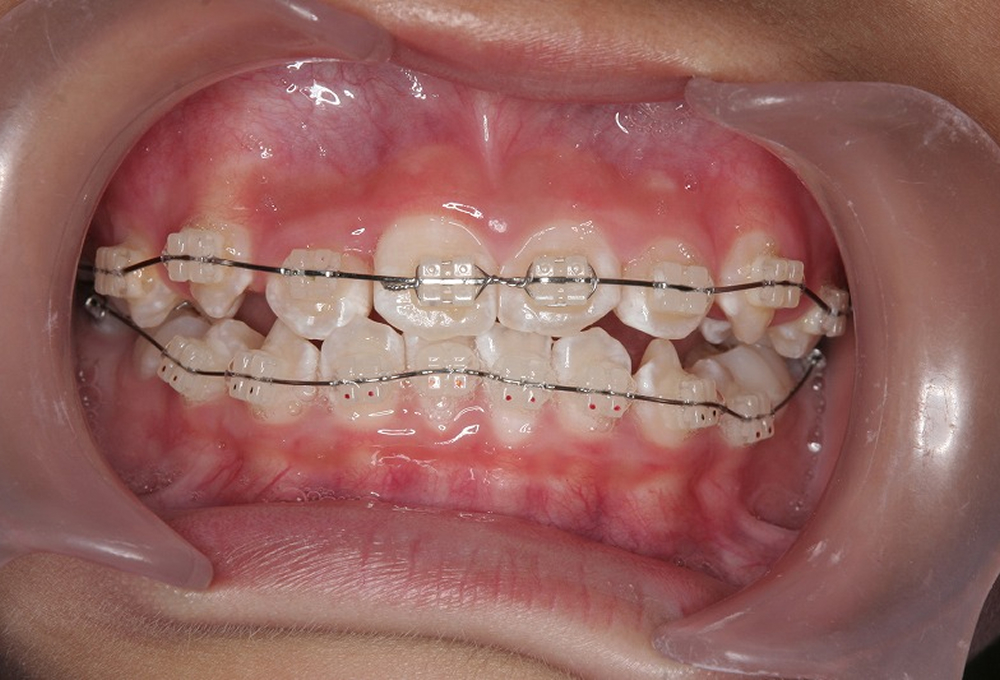

②マルチブラケットにて矯正